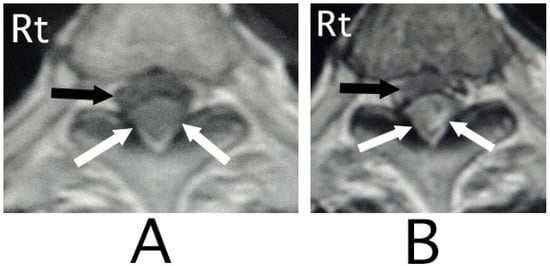

The lesion in the intracranial region or the cervical spinal cord was suspected. Computed tomography (CT) images of the head and X-ray of the cervical bone were normal; however, sagittal CT images of the cervical bone showed a slightly abnormal high-density area (HDA) behind the spinal cord at the level between C4 and C7 (Figure 3A). This abnormal HDA was located in the posterior part on the right side in axial CT images (Figure 3B). MRI analysis was performed because the presence of a hemorrhagic lesion was suspected, based on the CT findings of the cervical bone. Sagittal T1-weighted MRI showed an iso-intensity mass in the epidural space behind the spinal cord at the level from C4 to C7 (Figure 4A). The lesion was noted as a heterogeneous high-intensity mass in sagittal T1-weighted images (Figure 4B). Axial T1-weighted MRI showed an iso-intensity mass in the posterior part on the right side in the epidural space and mild compression of the spinal cord (Figure 5A). The lesion was noted as a heterogeneous high-intensity mass in axial T2-weighted images (Figure 5B).

Figure 4. Sagittal MRI. An iso-intensity mass was identified in the epidural space behind the spinal cord at the level from C4 to C7 (black arrows) (T1-weighted image; (A)). The lesion was visualized as a high-intensity mass with heterogeneity (black arrows) (T2-weighted image; (B)).